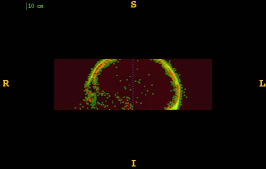

Figure 1 shows the examples of pixel selection masks generated using tested approaches at the highest resolution level for pixel sampling rate 0.5%. It is obvious that the samples generated with the URS approach are extremely spread, whereas the samples generated with the GMS approach are overly concentrated along the gradient magnitude structures present in the image. The proposed approach produces samples that balance those two extremities.